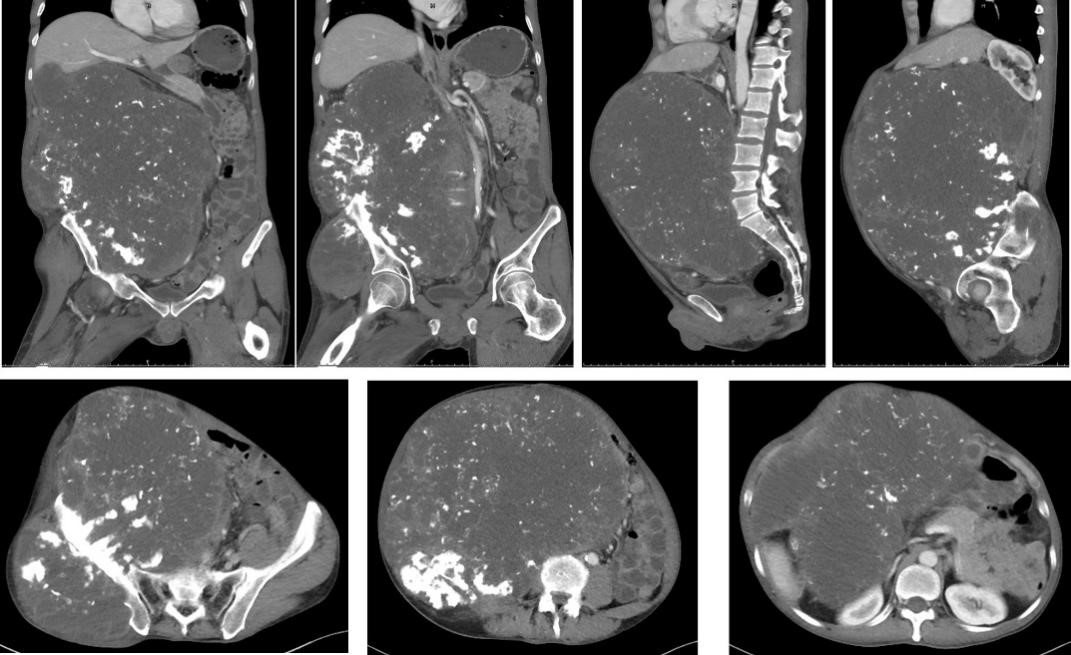

“他来到我们门诊时,由于肿瘤压迫腰骶部神经,行走困难。影像检查显示,肿瘤占据整个腹腔,肠子被肿瘤挤到一边,下腔静脉血管被压扁了。”中山大学附属第一医院骨肿瘤科邹昌业主任医师介绍,当时患者的情绪非常低落,如果再不及时采取干预措施,等待着他的将是被肿瘤活活“憋死”的结局。

CT检查结果显示肿瘤体积巨大

邹昌业随即发起全科讨论,沈靖南主任仔细研究患者影像资料后,认为患者为骨盆软骨肉瘤,肿瘤侵占半个多腹腔,肝肾、肠道、主动脉、下腔静脉等均受压移位明显,手术风险的确很大,且需要胃肠外科、血管外科、泌尿外科、麻醉科、手术护理等多学科团队保驾护航,“如果没有强大的多学科团队支持,就难以顺利地将肿瘤彻底切除。”